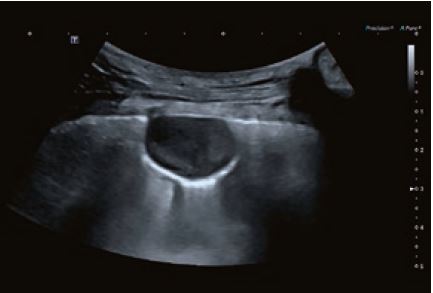

Випадок 2

Кішка, самиця, мейн-кун, два роки; на лікуванні від блювоти та схуднення протягом десяти днів; помірне збільшення обхвату при пальпації, УЗД кишківника з інвагінацією та затримкою газів; інтраопераційно: видалено 15 см кишківника; кішка почувається добре.